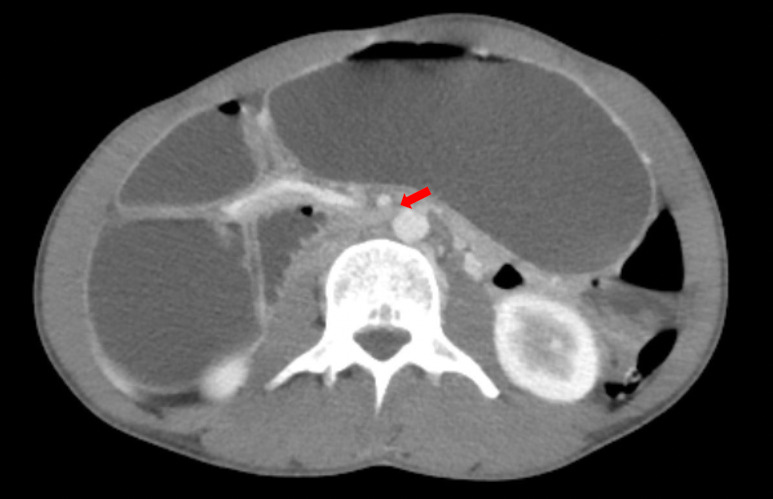

Introduction: Wilkie's Syndrome, also known as Superior Mesenteric Artery Syndrome (SMAS), is a rare cause of bowel obstruction that can contribute to vague abdominal symptoms on clinical presentation. This syndrome occurs when the aortomesenteric angle decreases, compressing the third portion of the duodenum between the aorta and the superior mesenteric artery. An acute decrease in the mesenteric fat pad cushion between these two blood vessels is the primary etiology, although other causes (e.g., anatomical, postoperative, functional, and pubescent etiologies) have also been described.

Case presentation: In the present cases, 2 females with a common history of recent weight loss presented to our institution with similar symptoms of abdominal pain, nausea and vomiting. Each patient was subsequently diagnosed with SMAS following imaging studies. Both patients experienced successful resolution of symptoms with conservative nutritional management.